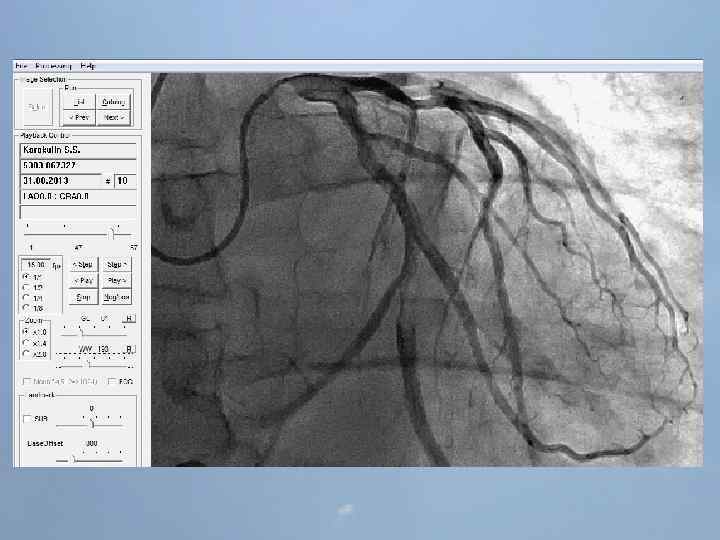

Концепции восстановления кровотока в инфарктзависимой артерии 1. Медикаментозная тромболитическая терапия 2. Рентгенэндоваскулярная – реканализация, БАП и стентирование инфарктзависимой артерии 3. Хирургическая – экстренное аутовенозное или артериальное шунтирование коронарных артерий В настоящее время в мире наиболее эффективным методом восстановления кровотока в инфарктзависимой артерии является коронарная ангиопластика и стентирование Б. Г. Алекян, А. В. Абросимов/Компл. проблемы сер. -сос. заболеваний. 2013, № 1

Преимущества ЧКВ перед ТЛТ 1. Немедленное определение коронарной анатомии и ранняя оценка степени риска 2. Лучшее обеспечение непосредственной проходимости сосудов и адекватного кровотока. 3. Меньшая частота реокклюзий, возврата ишемии, реинфаркта. 4. Лучшая выживаемость пациентов высокого риска. 5. Меньший риск внутричерепных кровоизлияний. 6. Возможность применения метода у пациентов с противопоказаниями к тромболизису. 7. Укорочение сроков госпитализации. • • Недостатки ЧКВ: необходимость в наличии квалифицированных специалиста и ангиографической установки задержка на время подготовки рентгеноперационной Недостатки тромболитической терапии 1. Возможность проведения тромболизиса только у 25 -33% пациентов с ИМ. 2. 20% сосудов после тромболизиса остаются окклюзироваными, а в 45% отмечается сниженный кровоток. 3. Среднее время, необходимое для наступления реперфузии, составляет 45 мин. 4. Отсутствуют клинические признаки, надежно отражающие наступление реперфузии. 5. Возврат ишемии наблюдается в 1530% случаев, внутричерепные кровоизлияния – в 0, 5 -1% случаев. Б. Г. Алекян, А. В. Абросимов/Компл. проблемы сер. -сос. заболеваний. 2013, № 1

Пациент Б. , 54 года 29. 08. 13 около 10: 00, находясь на рабочем месте, почувствовал боль в груди. После 2 -ух приемов нитроспрея боль не уменьшилась, вызвал СМП. В 10: 20 первой бригадой СМП зафиксирован подъем ST на ЭКГ, начата ТЛТ, вызвана реанимационная бригада. В 10: 50 на месте вызова в присутствии реаниматолога у пациента развивается остановка кровообращения по типу фибрилляции желудочков. Выполнялась СЛР с непрямым массажем сердца, ИВЛ мехом, дефибрилляцией. В течение транспортировки фибрилляция рецидивировала еще 4 раза. Пациент доставлен в ООКБ в 11: 30, минуя приемное отделение госпитализирован в ОРИТ ОИМ.